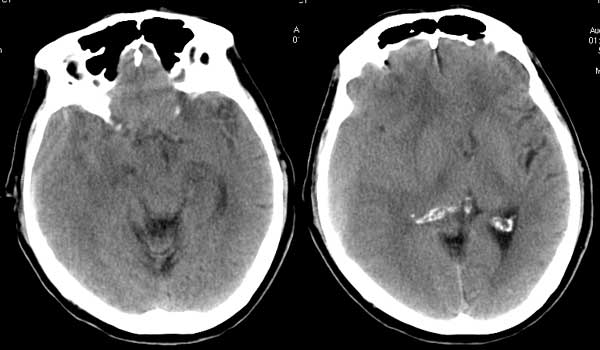

第一次片子:

第二天复查片子:

前两次的片子显示双侧额部均有病灶,三个月后复查,左侧吸收,右侧较前明显发展,呈浅s形,且以凹面为主,所以考虑慢性硬膜下血肿为主的血肿.并不能完全排除硬膜外血肿的可能,这个在影像上确实不好鉴别,必要是mr可以考虑查一下,或话有帮助.

此人前2次片比较典型的双侧额部硬膜下积液.并左侧少许出血灶,第三次片应该是硬膜下血肿,亚急性3天至3周才是等高密度影,所以说1.此人是否有新的外伤史,2.慢性硬膜下血肿再次出血.8楼兄弟说:\"前两次的片子显示双侧额部均有病灶,三个月后复查,左侧吸收,右侧较前明显发展\",我认为可能是右侧进展期,占位效应明显,推挤作用.

患者伤后第一次ct检查提示左额部蛛网膜下腔出血伴积液,右额部蛛网膜下腔积液。

第二天ct检查提示蛛网膜下腔出血吸收(或稀释)。

三个月后检查则见右额颞顶部混合形血肿(硬膜外血肿+硬膜下血肿),而双侧蛛网膜下腔积液基本消失。

从第一、二次ct片上看,患者受伤应该在右枕部,而硬膜下血肿对冲伤多见,因此,患者是否有第二次外伤史?

两侧硬膜下积液,三月后可见右侧硬膜下血肿。

最后手术结果硬膜下血肿